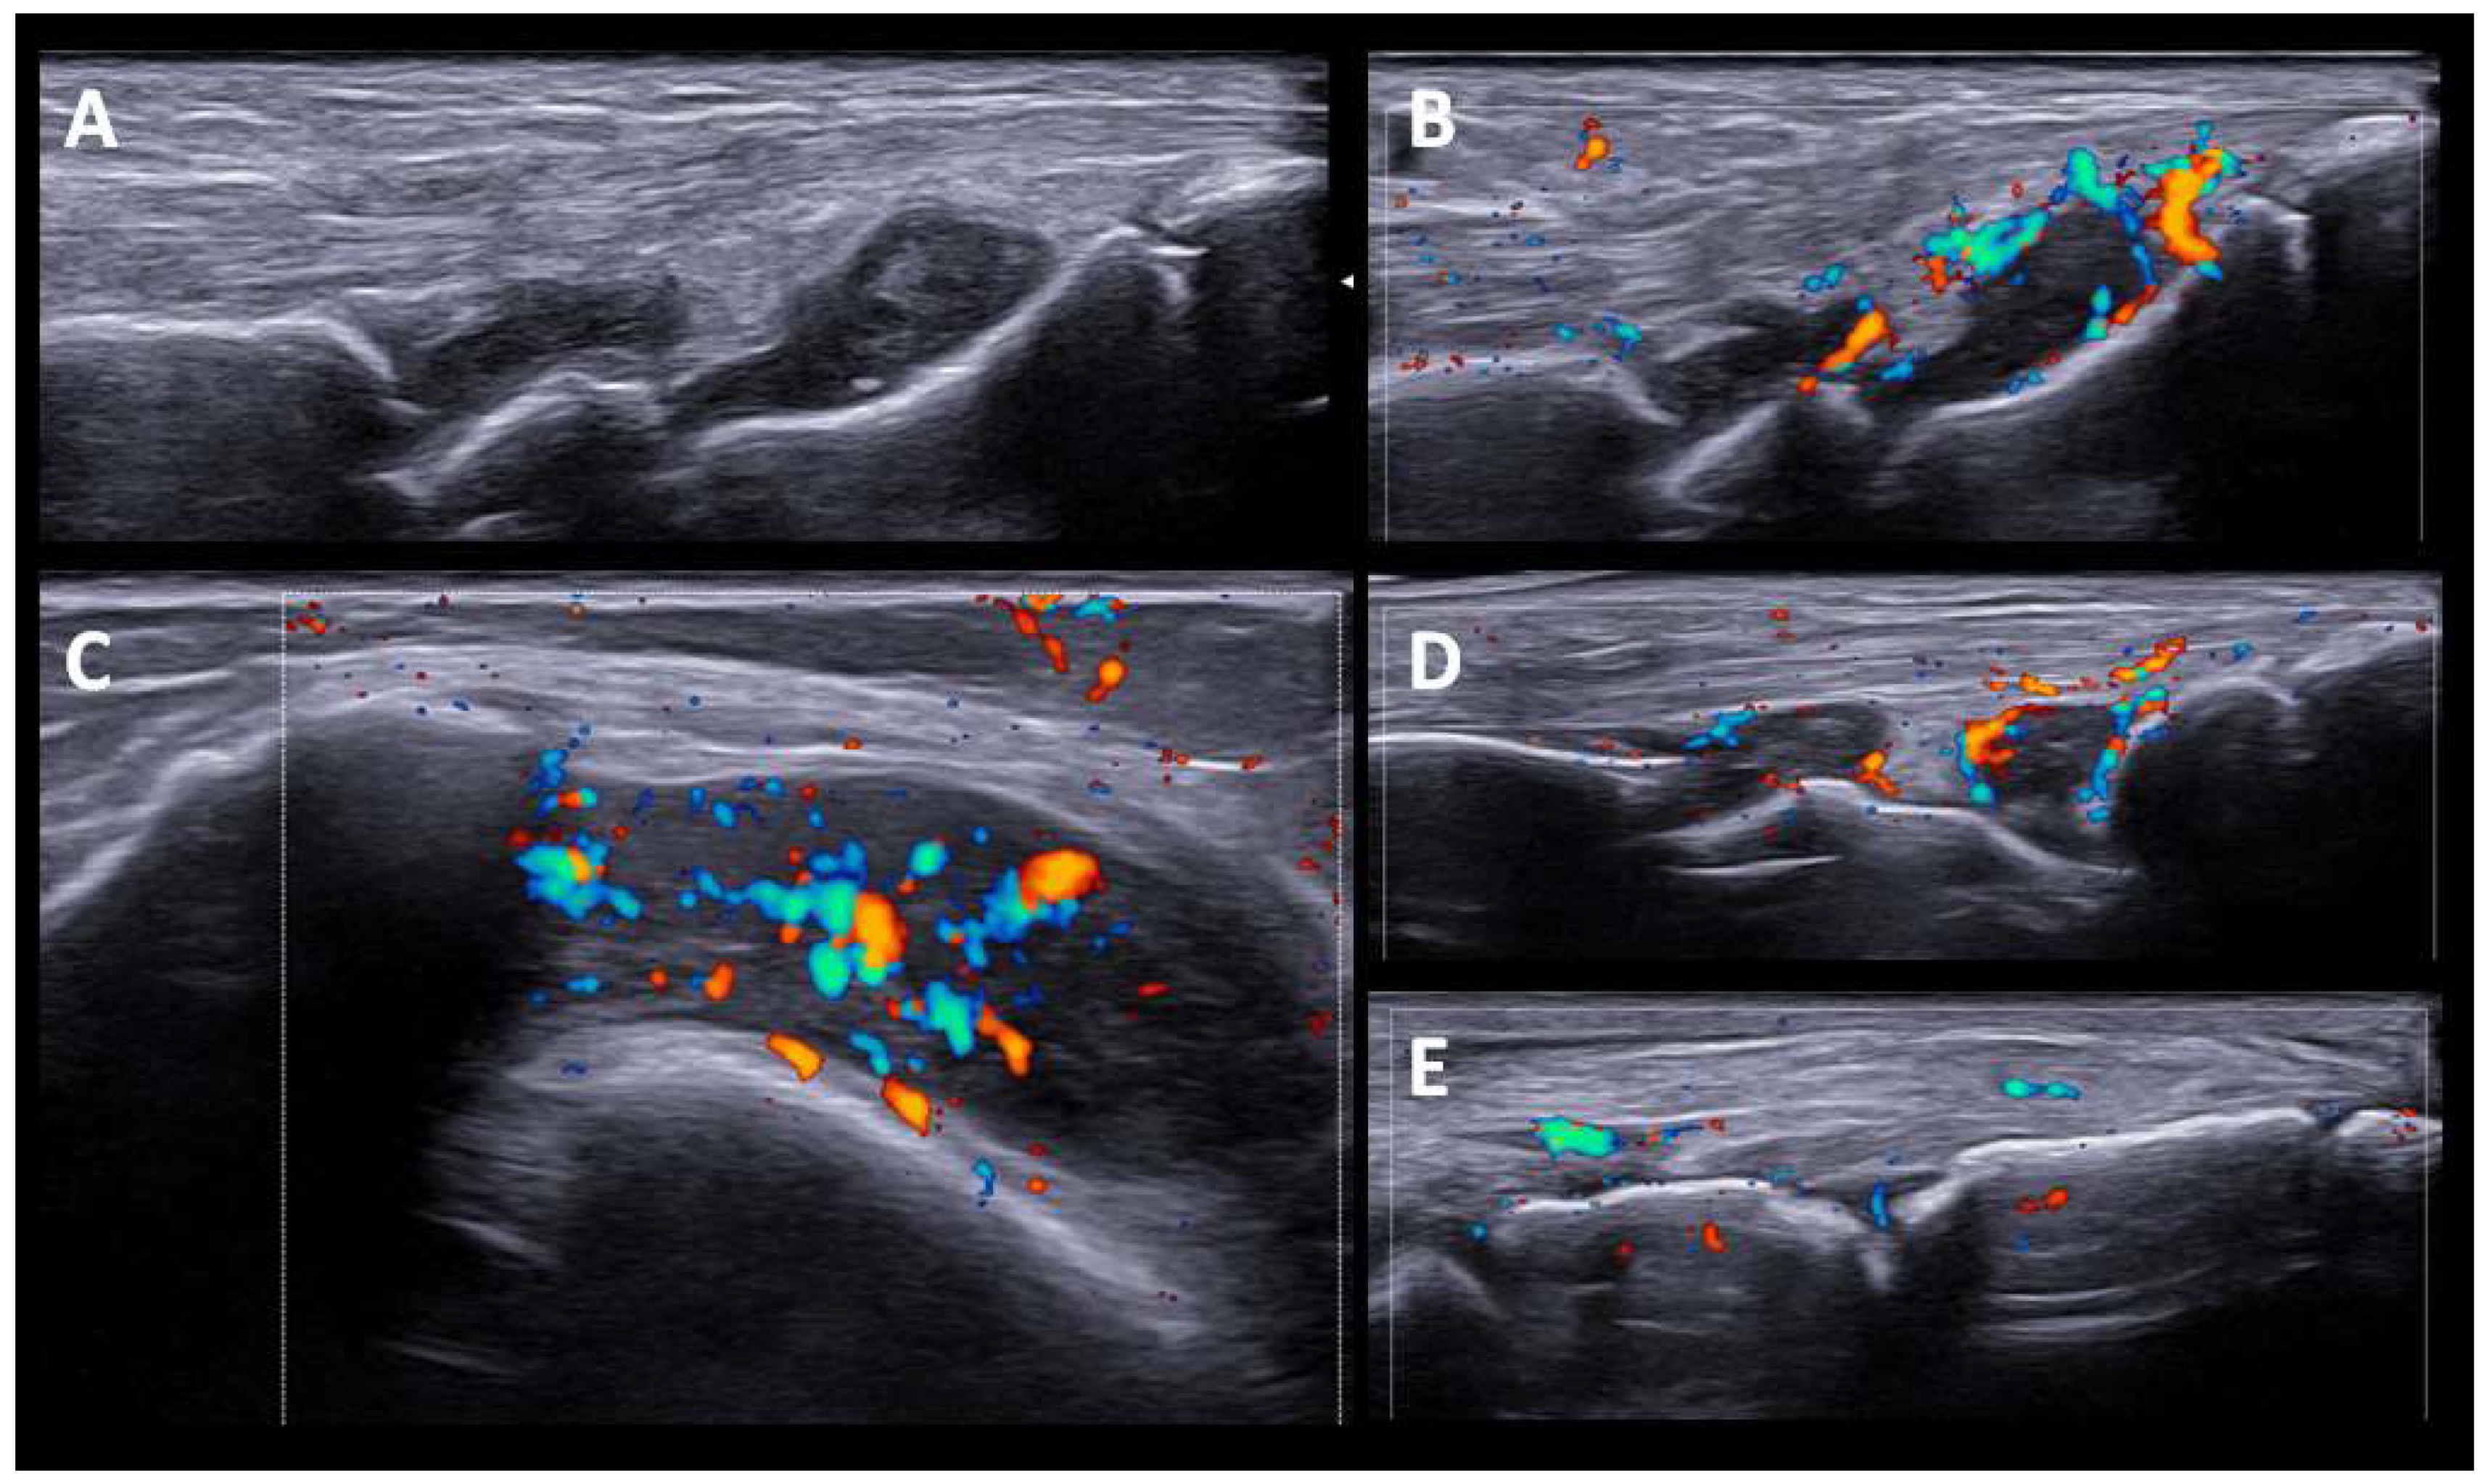

The US findings in RA-like patients were synovitis and tenosynovitis of the wrists and flexor tendon of the fingers. One patient also had synovitis in the knees and ankles, without involvement of the feet. Although they were seronegative (RF and anti-CCP), patients presented significant SH and PD signals, except for one patient treated with high doses of prednisone (40 mg/d). A set of US images with the most representative changes are shown in (Figure 1).

Figure 1.

US findings in RA-like pattern. (A,B). Carpal joint with synovial hypertrophy grade 2 and power doppler signal grade 2. (C). Knee suprapatellar recess shows synovial hypertrophy grade 3, and Power Doppler signal grade 2. (D,E). Tibiotalar, subtalar and tarsal joints with moderate synovitis and Power Doppler signal grade 2.

In our case series, US was performed after clinical assessment and as complementary information after physical examination. The US findings in patients with RA-like syndrome consisted of marked synovitis/tenosynovitis, although they were seronegative (anti-RF and ant-CCP), and presented high grades of SH and PD signals, with sonographic findings indistinguishable from typical RA. These US findings do not differ from those found in other series of patients with synovitis/tenosynovitis induced by ICI and studied by US [23].